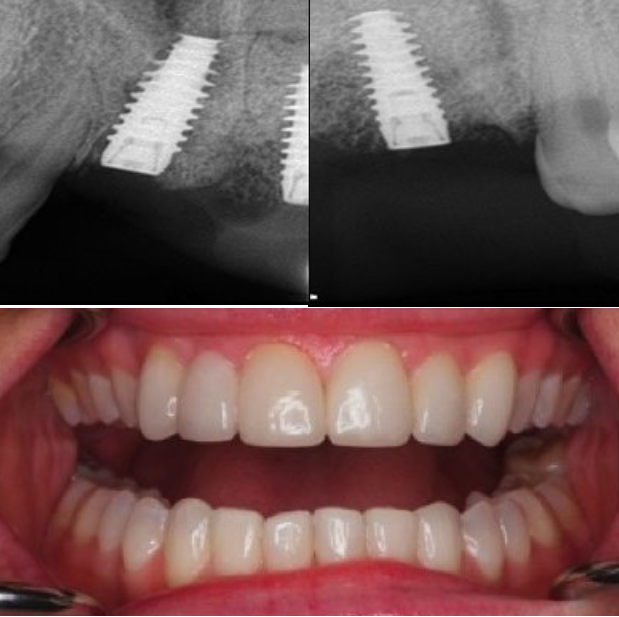

إذا كنت ترغب في الحصول على أسنان ولا تملك ما يكفي من العظام لإجراء علاج الزرع، لم يعد هناك حاجة إلى زراعة العظم من الآن فصاعدا.

تقدم زراعة الأسنان تحت السمحاق ثلاثية الأبعاد (3D subperiosteal implants) حلاً موثوقًا للحصول على أسنانك، خاصة في الحالات التي تكون فيها كمية العظام غير كافية لدعائم الزرع التقليدية.

عوده دون الحاجة إلى الخضوع لعلاج ترقيع عظمي واسع النطاق.

هذه التقنية ثورة في استبدال الأسنان!